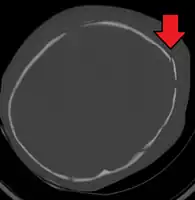

A skull fracture from abusive head trauma in an infant

3D CT reconstruction showing a skull fracture in an infant